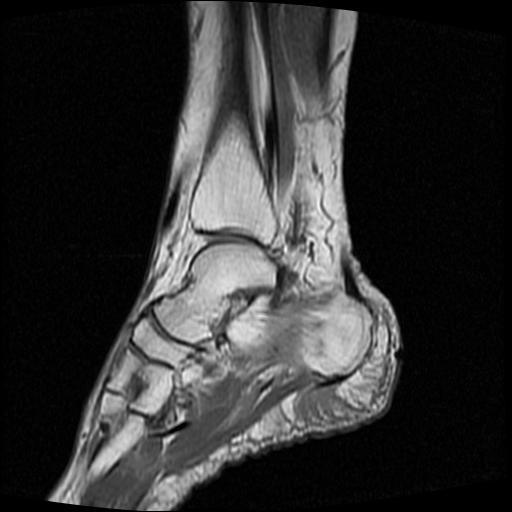

标题: MRI0968:女性,70岁,跟骨信号异常 [打印本页]

标题: MRI0968:女性,70岁,跟骨信号异常

女性,70岁,右侧跟骨疼痛2个月,负重时加剧,不负重时不疼。

胫骨下段,跟骨、距骨可见斑片状异常信号区;考虑:转移瘤

跟骨长t1长t2信号异常,边缘模糊(肿瘤一般边界清楚,故肿瘤不考虑),压脂像呈高信号--骨髓水肿(炎症?)。